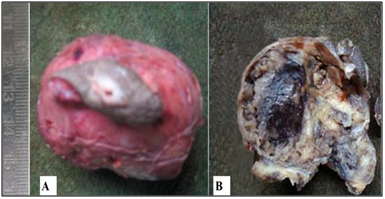

A 54 year-old male presented to the surgical out-patient department. He complained of lower backache and swelling in the gluteal region since many years. The swelling had gradually progressed to the present size. There was a recent rapid increase in size of swelling, accompanied by formation of a discharging sinus of three months duration. On examination, a 5 X 4 cm mass was present in the intergluteal fold, the overlying skin showed a discharging sinus measuring 1 X 1 cm (Figure 1). Clinical diagnosis of Pilonidal sinus was made. Routine investigations were within normal limits. The patient was referred for fine needle aspiration cytology. The smears showed abundant myxoid stroma with singly dispersed small, round cells with bland nucleus along with cells having abundant vacuolated bubbly cytoplasm and small nucleus (Figure 2). A diagnosis of myxoid rich soft tissue tumour with possibility of chordoma was suggested. Lumbar magnetic resonance imaging done subsequently revealed a well demarcated, multilobulated mass in the sacococcygeal region (Figure 3).

The mass was excised and sent for histopathological examination. Gross examination showed a circumscribed soft tissue mass covered with an elliptical piece of skin with ulceration and sinus formation. Cut surface was firm to hard, vaguely lobulated and variegated with reddish brown hemorrahagic to gelatinous areas (Figure 4). Histopathology revealed a tumour composed of cells arranged in lobulated pattern separated by fibrous septa. The stroma showed myxoid areas and areas of hemorrhage and necrosis. The tumour cells were polyhedral to round with eosinophilic cytoplasm and round atypical nuclei along with physaliphorous cells. Occassional spindle shaped stellate cells and signet ring-like cells were also seen. Physaliphorous cells were large multivacoulated with bubbly appearance of cytoplasm and small inconspicuous nuclei (Figure 5). The cytoplasmic vacuoles were periodic acid Schiff (PAS) positive and diastase sensitive suggesting glycogen deposition (Figure 6). The tumour cells were seen infiltrating the capsule and surrounding soft tissue. The skin overlying tumour showed ulceration and chronic inflammatory cell infiltrate in the dermis. Diagnosis of sacrococcygeal chordoma- NOS was made.